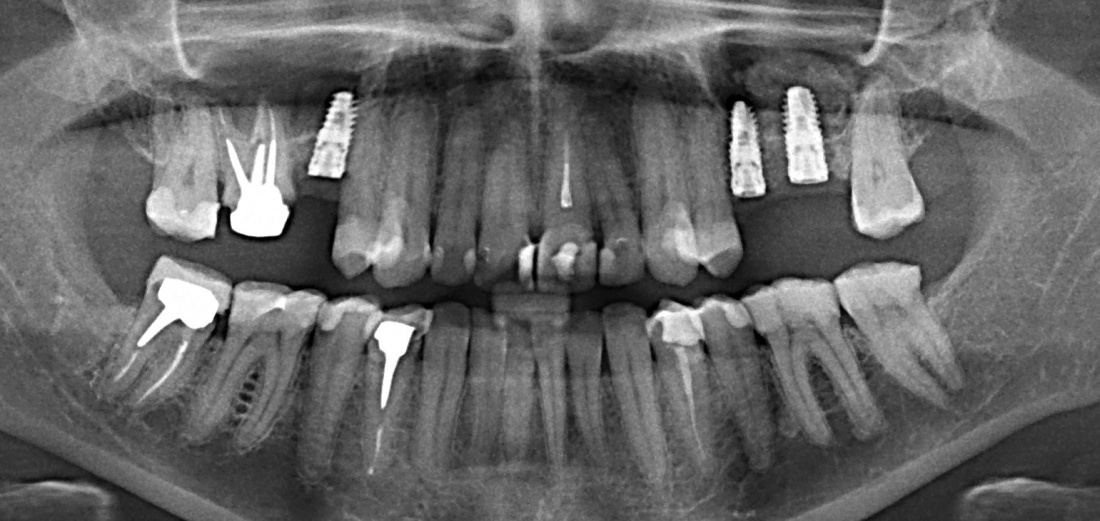

В общем, так и получилось. Уж не помню, почему я наобещал пациентке, что мы поставим ей имплантаты одновременно с остеопластикой. Но я наобещал. И, когда увидел клиническую картину в полости рта:

у меня появились серьезные сомнения, смогу ли я выполнить своё обещание. Вот только не спрашивай меня «Вот чо, сложно было по КЛКТ посмотреть?». Я же не спрашиваю тебя, где ты был в 2013 году, и сделал ли ты домашку. Но, в целом, план операции у нас не поменялся. Как и было оговорено, мы проведем остеопластику с одновременной имплантацией в боковом участке нижней челюсти справа.

Кстати, обрати внимание на ширину альвеолярного гребня (левая картинка). Она чуть меньше 3 мм. Это объясняет, почему я засомневался в возможности установки имплантатов одновременно с остеопластикой. Понятно и без КЛКТ.

Возвращаемся к основной операционной области. Еще раз посмотрим на альвеолярный гребень, поофигеваем от его ширины и моих грандиозных планов:

— контрольный снимок (раньше делали ОПТГ, сейчас — строго КЛКТ)

Для этого мы сделали КЛКТ:

И КЛКТ показала нам, что с имплантатами и окружающей костью всё зашибись. Через 12 лет после операции, отсутствия наблюдения, пофигизма в замене временных коронок! Нужны ли тебе еще какие-нибудь доводы в пользу долгосрочной эффективности метода?

Серия контрольных снимков на этапах: